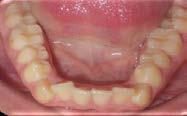

El examen clínico intraoral reveló una clase I molar bilateral, caninos superiores en infraoclusión, por ende la clase canina no se puede clasificar, presencia de apiñamiento severo, rotaciones en premolares superiores e inferiores, línea media inferior desviada hacia el lado derecho 3.5 mm,

falta de coordinación de las arcadas, el arco inferior con forma cuadrada y el superior forma ovoide, el overjet de 2 mm y el overbite de 2 mm (Figura 2).

Figura 2. Fotografías intraorales iniciales.